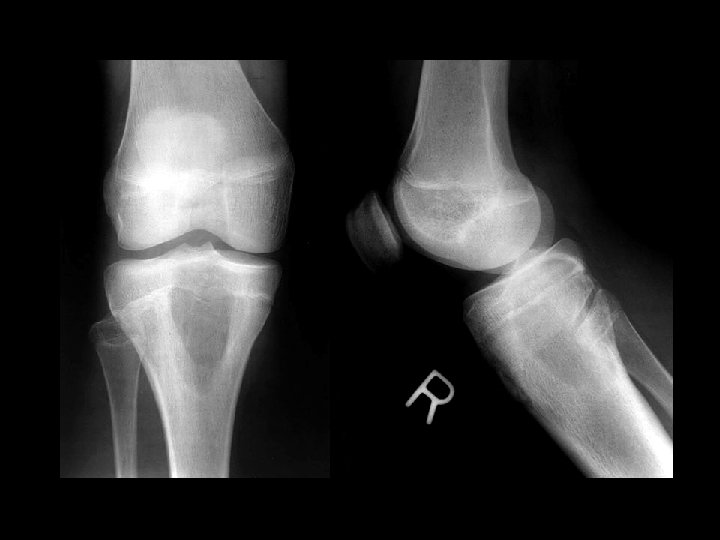

Aneurysmal bone cyst • Findings: – Lucent end of bone lesion in the proximal tibia – Slightly expansile, mild periosteal reaction – Fluid-fluid level on MRI • ddx: – Giant cell tumor – Unicameral bone cyst – Fibrous dysplasia – Chondroblastoma (rare)